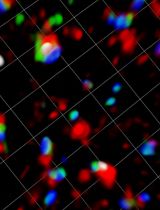

Figure 2. Plate map and example images following assaying of a GFP-LUHMES 384-well plate drug screen. A. Plate map showing the suggested arrangement of control wells and test compound wells. All wells are treated with rotenone except for “DMSO vehicle” wells. The colours represent the concentration in nM for each compound. B-D. Blue = DAPI, orange = TMRM, green = GFP, scale bars = 20 μm. Z stack maximum projection confocal images captured using the Opera Phenix High-Content Screening System from (B) a vehicle-treated DMSO control well, (C) a rotenone-treated DMSO control well and (D) a rotenone-treated positive control well (1,000 nM).

Write an imaging protocol (details below) for imaging the LUHMES cells on the Harmony High-Content Imaging and Analysis Software. Use the DAPI, Alexa 488 and Cy3 channels to capture the Hoechst signal, GFP signal and TMRM signal respectively. Use test images to ensure appropriate exposure time for each laser; this needs to be set by the user as it depends on the signal strength of laser power of each imaging system. Use a 40x water confocal objective, set the number of fields to 10 and set the number of stacks to 6. Select the wells to be imaged (note the outermost two columns and rows cannot be imaged by the Opera Phenix) and select the location of the fields in each well.